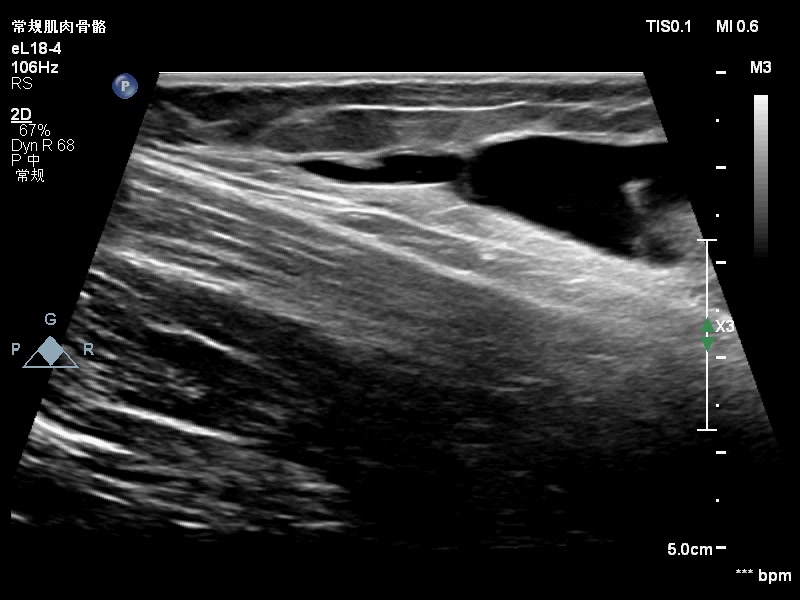

范特西_ 推荐男孩,12y,骑自行车过程中摔倒,右大腿内侧撞到了路边护栏,已有4-5天,今因大腿内侧肿胀就诊,声像图如下:

感觉是脂肪层和深方的深筋膜分离后积血。?所示应该是深筋膜吧。

大家考虑脱套伤吗?在报告中应怎么诊断?望各位老师指点。